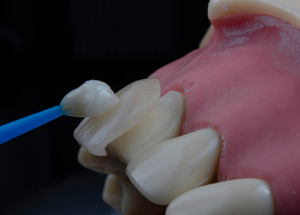

Наша галерея